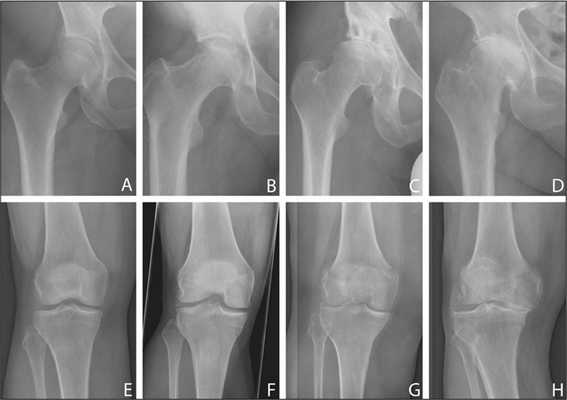

Как проявляется ревматоидный артрит

Серопозитивный ревматоидный артрит на данный момент не имеет четко обозначенных причин возникновения, представляя собой заболевание, спровоцированное комплексом влияющих факторов. Имеет ряд симптомов, затрагивающих суставы кисти рук и другие органы, выраженность которых зависит от стадии развития и тяжести течения болезни:

Для этого заболевания характерно симметричное поражение суставов, как крупных – коленных, локтевых, так и мелких суставов кистей. Суставы кисти поражены в 90% случаев. По мере развития патологии возникает деформация суставов. Кроме сочленений, серопозитивный ревматоидный артрит поражает также соединительную ткань других органов и систем, что вызывает тяжелые нарушения их работы.